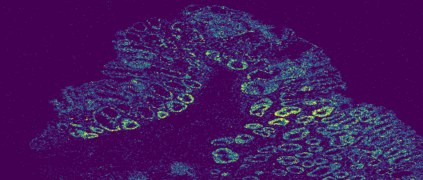

The usage of chemical imaging technologies is becoming a routine accompaniment to traditional methods in pathology. Significant technological advances have developed these next generation techniques to provide rich, spatially resolved, multidimensional chemical images. The rise of digital pathology has significantly enhanced the synergy of these imaging modalities with optical microscopy and immunohistochemistry, enhancing our understanding of the biological mechanisms and progression of diseases. Techniques such as imaging mass cytometry provide labelled multidimensional (multiplex) images of specific components used in conjunction with digital pathology techniques. These powerful techniques generate a wealth of high dimensional data that create significant challenges in data analysis. Unsupervised methods such as clustering are an attractive way to analyse these data, however, they require the selection of parameters such as the number of clusters. Here we propose a methodology to estimate the number of clusters in an automatic data-driven manner using a deep sparse autoencoder to embed the data into a lower dimensional space. We compute the density of regions in the embedded space, the majority of which are empty, enabling the high density regions to be detected as outliers and provide an estimate for the number of clusters. This framework provides a fully unsupervised and data-driven method to analyse multidimensional data. In this work we demonstrate our method using 45 multiplex imaging mass cytometry datasets. Moreover, our model is trained using only one of the datasets and the learned embedding is applied to the remaining 44 images providing an efficient process for data analysis. Finally, we demonstrate the high computational efficiency of our method which is two orders of magnitude faster than estimating via computing the sum squared distances as a function of cluster number.